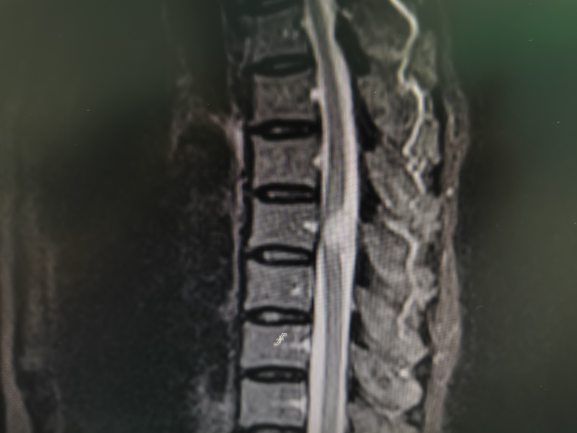

時隔4年,李雪松醫(yī)生依舊那般親切,讓人心生溫暖。經(jīng)過詳細(xì)的診查和評估,劉奶奶被確診為胸12椎椎管內(nèi)占位,這意味著她的椎管里長腫瘤了,初步考慮是良性神經(jīng)鞘瘤!劉奶奶得知此情況后十分擔(dān)心,更為自己再一次被腫瘤“盯上”而悲傷。

李雪松博士與家人解釋道:“目前來看,腫瘤壓迫到了脊髓,手術(shù)切除是最好的治療方法,但是患者年齡大,手術(shù)風(fēng)險相對高一些,如果不做手術(shù),后續(xù)的生活質(zhì)量會越來越差,隨著腫瘤的生長,可能會面臨大小便失禁、癱瘓的風(fēng)險,我的建議是在電生理監(jiān)測下,用顯微鏡將腫瘤安全切除。”

因為劉奶奶的椎管內(nèi)腫瘤位置特殊,占位效應(yīng)明顯,為保障手術(shù)順利實施,惠州三院神經(jīng)外科團隊在術(shù)前進行了全面、詳細(xì)的手術(shù)規(guī)劃。在醫(yī)患互信和充分的術(shù)前準(zhǔn)備下,李雪松博士和神經(jīng)外科團隊成功為患者施行椎管內(nèi)腫瘤切除術(shù)。術(shù)中,主刀醫(yī)生李雪松博士、助手胡永珍副主任醫(yī)師憑借多年的手術(shù)經(jīng)驗和嫻熟的手術(shù)技巧,小心巧妙地分離出腫瘤邊界,完整切除了腫瘤。術(shù)中脊髓電生理監(jiān)測波幅平穩(wěn),表明手術(shù)操作對脊髓干擾輕微,預(yù)示著神經(jīng)功能恢復(fù)良好。